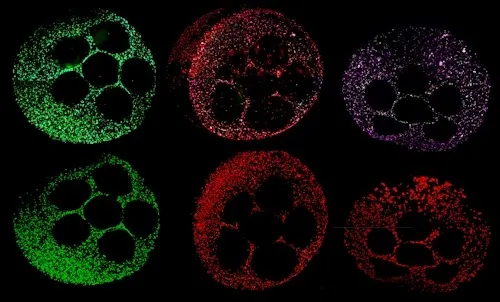

肝臓オルガノイドは、前臨床段階で薬剤性肝障害をおよそ80%の精度で予測します。オルガノイドを用いた薬剤性肝障害の予測は、薬剤の安全性を向上させ、新しい治療法の発見を加速し、薬剤障害の主な原因をより迅速に特定することができます。ダナハー、モレキュラーデバイス、シンシナティ小児科の幹細胞・オルガノイド医学センター(CuSTOM)の協力により、肝臓オルガノイドのスケールアップ生産を可能にするハイスループット技術が実現します。これには、細胞バンクを構築し、ヒトの遺伝子をよりよく反映させ、臨床試験における多様性を向上させる構想も含まれています。

オルガノイド科学を発展させるために私たちが抱いている中核的な信念は、オルガノイドの生成から当て推量を取り除くことです。CellXpress.aiプラットフォームのような自動化技術の設計は、その信念を支えるものです。例えるなら、このテクノロジーは、細胞を入れるとオルガノイドが出てくるオーブンのようなものです。オーブンに例えるなら、すぐに使えるケーキミックスが理想的なアプローチです。このエンドツーエンドを達成するために、私たちは、スクリーニング・ツールとして使用するためにスケールアップする際に再現性と一貫性を確保できるよう、標準的な方法と品質管理を浸透させることによって、次のレベルに引き上げることに注力してきました。

方法、培地、プロトコルを微調整するために、かなりの量の作業を前もって行う必要があります。これは、何かが革新的なモデルから主力技術へと進歩するための基本的な側面です。例えば、ある患者のセルに特異性レベルで作用するように最適化された方法が、別の患者に合うように条件を調整する必要がないとは限りません。スケーラビリティの問題に対処するために必要なのは、大規模な患者サンプル集団で機能する適切な方法と条件を見つけることです。これがCuSTOMが完成させる作業です。完成後は、細胞が穏やかに扱われ、ストレスを受けず、自発的に分化していることなどを確認するために、結果を検証する必要があります。モレキュラーデバイスは、当社のCellXpress.aiプラットフォームと専門知識を活用して支援します。

特異的な薬剤性肝障害など、ある種の肝臓の感受性は、遺伝的要素が大きいのです。セルが行っているのは、例えば、さまざまな民族の患者を集めた細胞バンクの設立です。これは、低リスク、中リスク、高リスクの患者からオルガノイドを作製し、試験管内で薬物治療後のシグナルが見られるかどうかをテストする対物レンズによるスクリーニング・プラットフォームの基礎となります。このアプローチを用いれば、科学者は臨床試験に入る前に、何を調べるべきか、どのように投与量を設定すべきか、どのようにスクリーニングすべきか、基本的にはどのようにリスクをより効果的に軽減すべきか、がわかるようになります。これは非常に重要なことです。皿の中の患者という概念。生体内に入る前に、実際に何が起こるかを知ることができますか?複雑なモデルやオルガノイドのような概念が真に輝くのはこの点です。

歴史的に、肝毒性などは知られていましたが、医薬品開発に関しては十分に追跡されていませんでした。肝毒性は急性肝不全につながる可能性があり、これは不可逆的なダメージです。2020年当時、私が特に印象に残っているのは、死亡事故が発生したためフェーズ2で中止せざるを得なかった2つの薬剤の臨床試験です。開発の早い段階で毒性が確認されていれば、このような事態は避けられたはずです。ミシガン大学の研究者たちは、肝臓モデル(CCHMCで開発されたオルガノイドモデルに類似)をスクリーニングアッセイとして使用していれば、試験管内で薬物の毒性が確認できたことを示し、リソースを大幅に節約し、最も重要なことは患者の命を守ることでした。